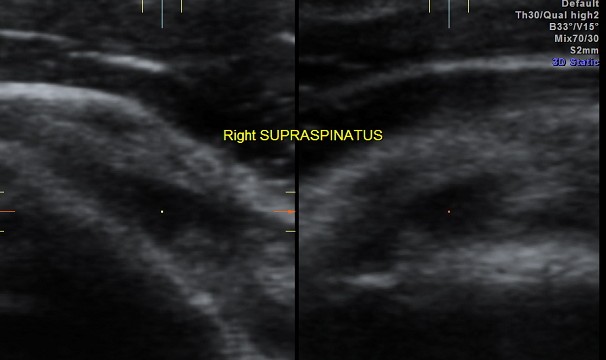

SUPRASPINATUS TEAR Date: May 27, 2012Author: kriznan Category: Shoulder, Musculo-skeletal ultrasound Tags: MUSCULO SKELETAL ULTRASOUND, PARTIAL TEAR, SHOULDER ULTRASOUND, SUPRASPINATUS TEAR Post navigation ← NON IMMUNE HYDROPS VESICAL CALCULI → This slideshow requires JavaScript.For imaging the rotator cuff, we need the high resolution transducer and appropriate positioning ; for the supraspinatus , I prefer the patient keeping his hand (of the side of the shoulder being examined ) in the opposite back pocket position Share this: Share on X (Opens in new window) X Share on Facebook (Opens in new window) Facebook Email a link to a friend (Opens in new window) Email Share on LinkedIn (Opens in new window) LinkedIn Share on WhatsApp (Opens in new window) WhatsApp More Print (Opens in new window) Print Share on Reddit (Opens in new window) Reddit Share on Tumblr (Opens in new window) Tumblr Share on Pinterest (Opens in new window) Pinterest Share on Telegram (Opens in new window) Telegram Like Loading...